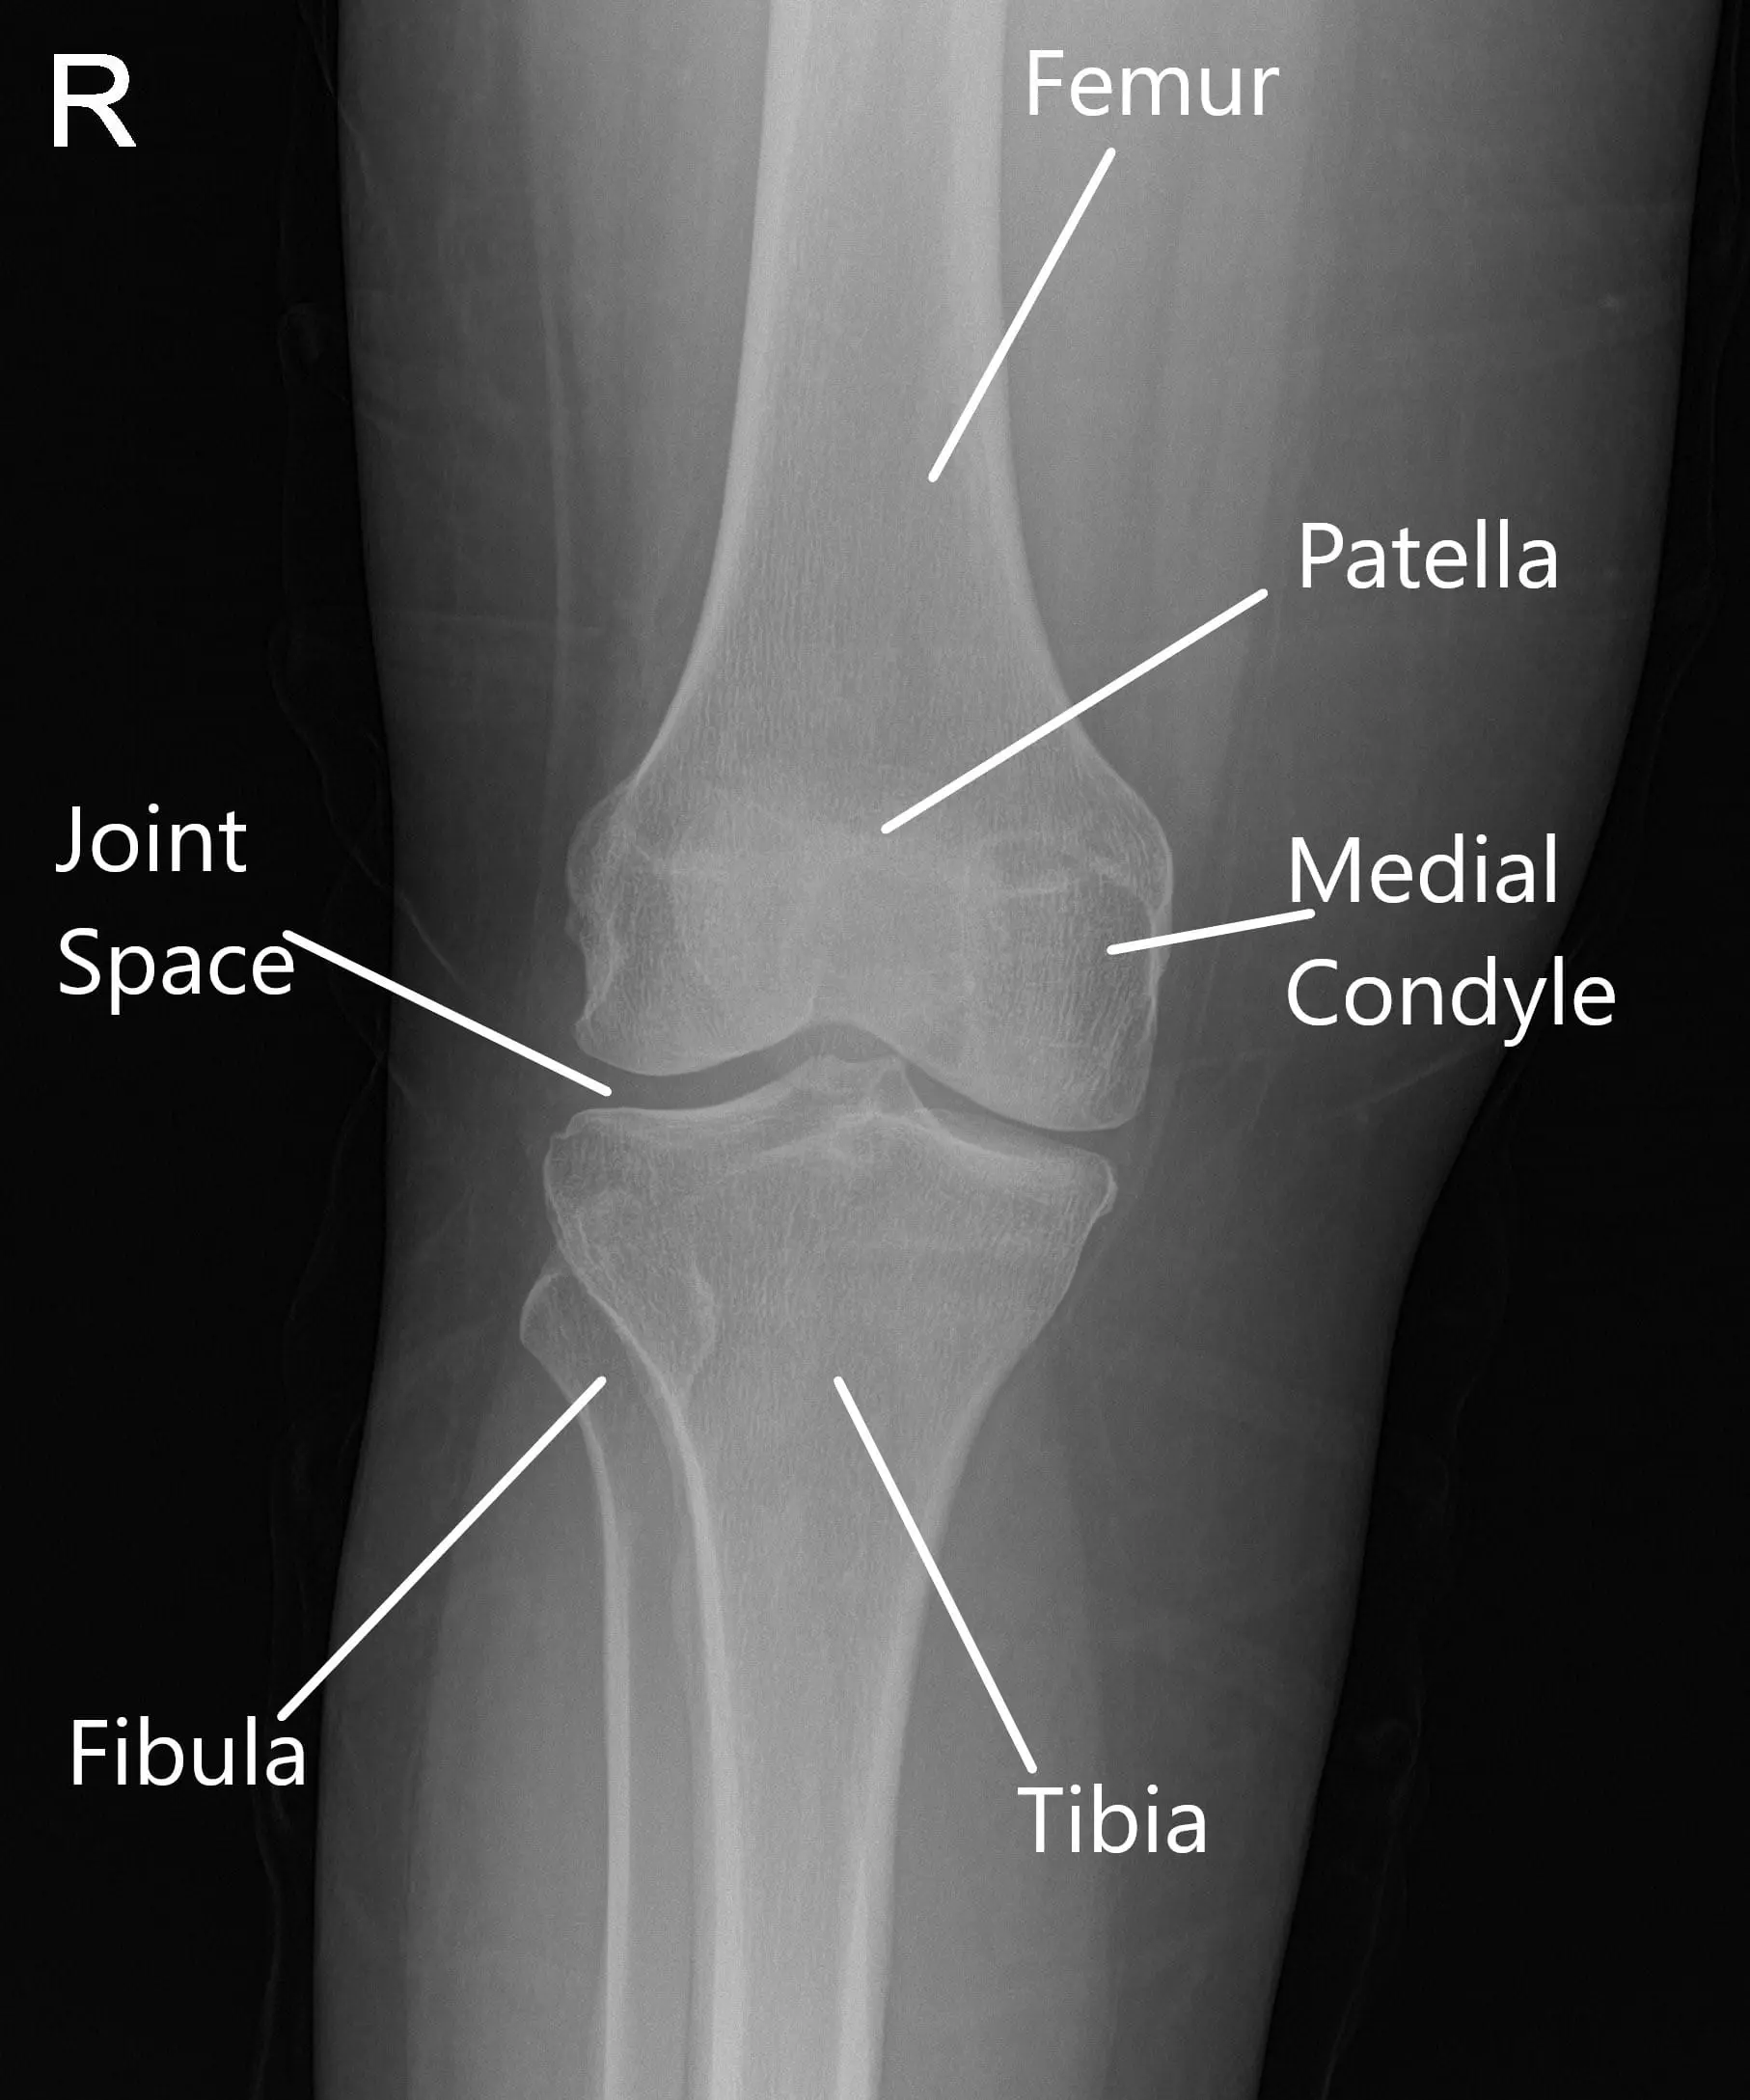

X-Ray of the right knee suggested mild osteoarthrosis in the medial and anterior compartment of the knee.